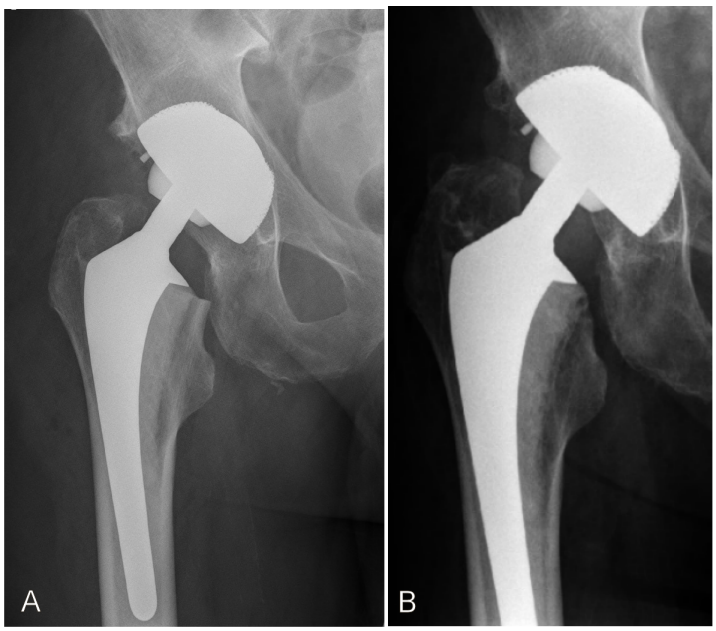

Figure 1: Postoperative X-ray of the right hip 4 days after operation (A) and 8 years later (B).

The X-ray 8 years later (B) was done in an external clincic, so unfortunately the complete endosprosthesis is not illustrated. The metaphyseal part shows no loosing. The patient is content and has no symptoms or complaints. Therefore, a current x-ray imaging is unnecessary.

The preoperative planning showed that the second largest cementless titanium-covered femoral stem would be adequate. Yet, intraoperative probation showed that the largest cementless stem was too small. An experienced allergologist was consulted during surgery. There were two options to consider: Girdlestone and second setting implantation of a custom-made or specially ordered large titanium-covered stem or risking implantation of cemented nickel-containing non-titanium covered stem. In this case we favored the second option and planned for postoperative control in the department of allergology. The postoperative course was without any complications (Figure 1A [Fig. 1]). After 3 months, the patient consulted the allergologist. To prevent iatrogenic sensitization, a patch testing of nickel-sulphate and potassium-dichromate was deliberately avoided. Clinical examination was sufficient and it showed no pathological findings.

Eight years after implantation of nickel-containing cemented femoral stem, the current clinical examination shows no general or local pathological signs (Figure 1B [Fig. 1]). The patient is content and does not report any general or orthopedic complaints. Walking aids are not used, painkillers are not taken and the walking distance is unlimited. The right hip shows a free range of motion: extension/flexion 0/0/90°, abduction/adduction 40/0/30°, external rotation/internal rotation 45/0/30°. Further, clinical examination shows equal leg length, no Trendelenburg’s sign and intact peripheral circulation and neurological findings.